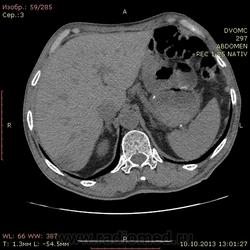

69 лет. КТ контроль от августа. Посте очередного курса химии. Начало истории здесь http://www.radiomed.ru/cases/kt-bryushnoi-polosti-adenokartsinoma-zheludka-sostoyanie-posle-rezektsii-zheludka-mts-v-pechen

Сегодня выглядит так. DICOM здесь http://files.mail.ru/2A18DCE6A6AA4546B51713D2F9C9E91A

На мой взгляд метастазов новых нет, но старые увеличились и один из пораженных л\у также увеличился.